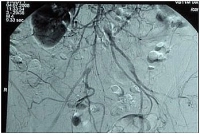

Preoperative intra-arterial DSA

PM 303-1

High aortic occlusion in bifurcation stenosis